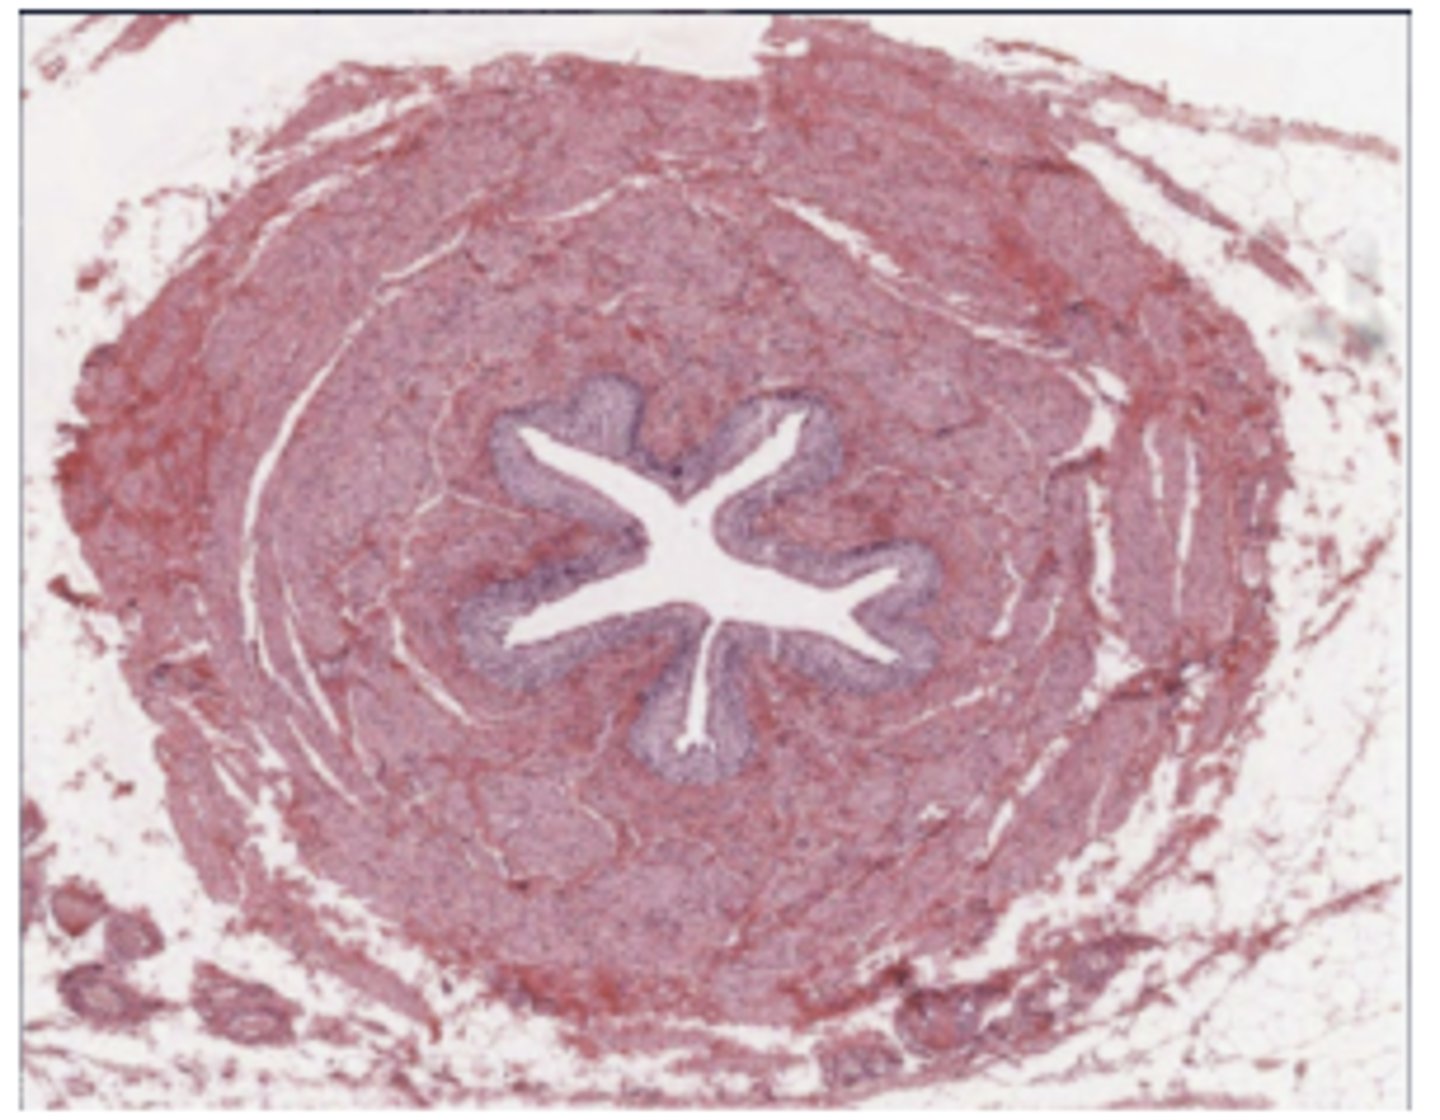

ureter

Bowman's capsule